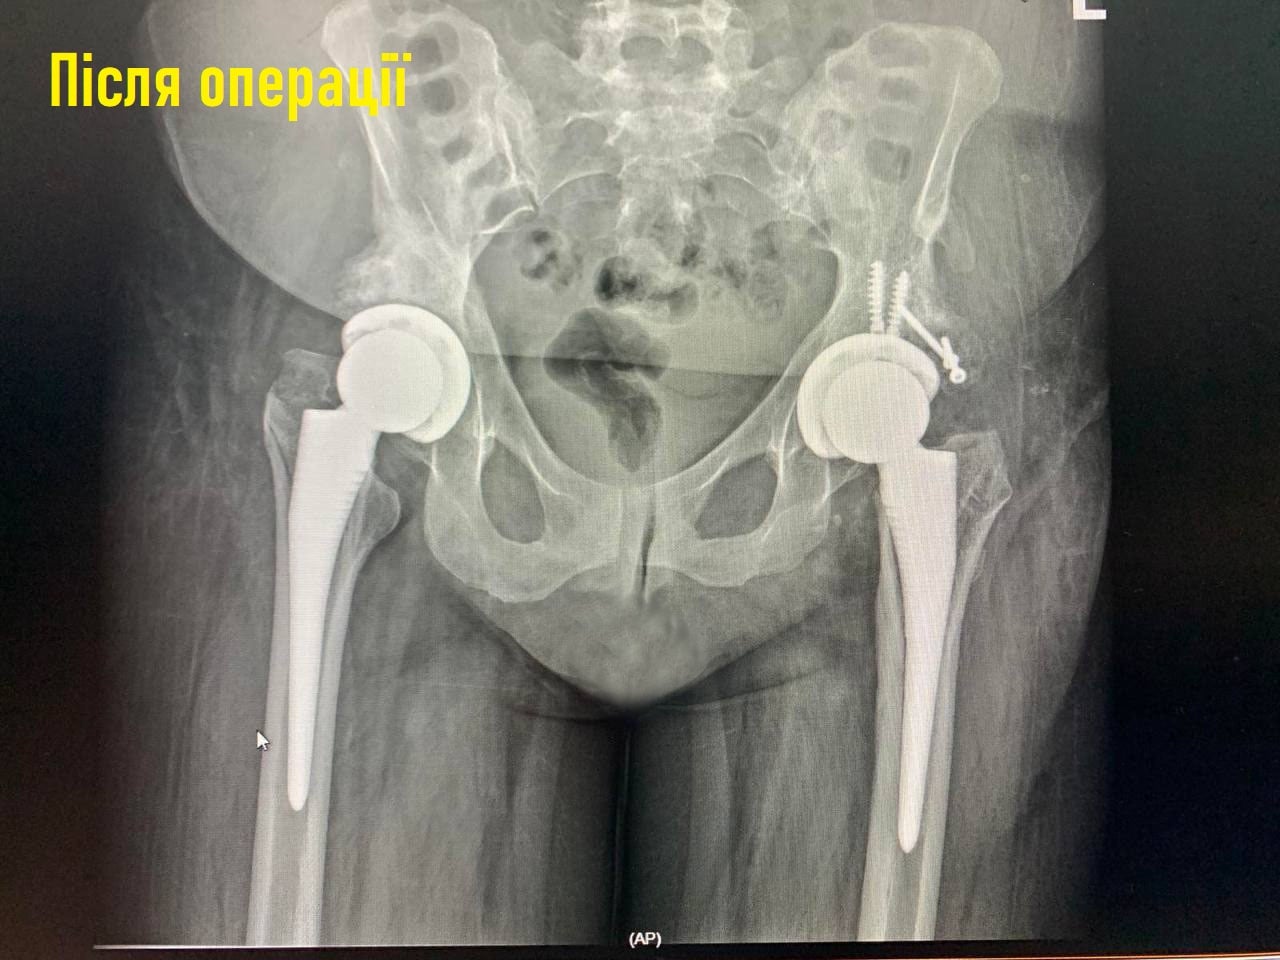

Щоб відновити втрачені функції суглобів та повернути жінці можливість вільно рухатися, команда професіоналів прийняла виклик. Бригада лікарів на чолі з Богданом Байчуком провела одномоментне ендопротезування кульшових суглобів безцементною системою.

Крім того, з однієї сторони було проведено пластику западини без додаткових розрізів.

Уже наступного дня після операції хвора ходила на нових суглобах без болю та обмеження рухів. На десятий день жінку виписали з лікарні та вона самостійно пішла додому.